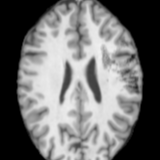

FLAIR(ISLES)FLAIR(ISLES)T1w(ATLAS)T1w(ATLAS)FailedInputSynthSRBrain-IDPEPSIUNALesionRefer to captionRefer to captionRefer to captionRefer to captionRefer to captionRefer to captionRefer to captionRefer to captionRefer to captionRefer to captionRefer to captionRefer to captionRefer to captionRefer to captionRefer to captionRefer to captionRefer to captionRefer to captionRefer to captionRefer to captionRefer to captionRefer to captionRefer to captionRefer to caption

Figure 4: Qualitative comparisons on healthy anatomy reconstruction between UNA and state-of-the-art modality-agnostic synthesis models. Testing images are from real stroke datasets (ISLES [22] and ATLAS [36]), where the stroke lesion annotations are provided, yet the ground truth healthy anatomy is unavailable. The last row shows a failure case of UNA, where it “over-corrects” the diseased anatomy. Pathology regions are circled in red.

We further evaluate UNA’s performance on all the real datasets as introduced in Sec. 5, among which ATLAS [36] and ISLES [22] contain stroke patients. Tab. 2 reports the reconstruction scores over all datasets and their available modalities: (i) For anatomy reconstruction of originally healthy subjects, UNA achieves the highest scores across most datasets, with the remaining scores on par with Brain-ID [38], which is specifically designed for healthy anatomy; (ii) On the ATLAS stroke dataset, UNA outperforms competing models by a larger margin (10%absentpercent10\approx 10\%≈ 10 %).

As shown in Fig. 4, other models tend to generate unrealistic patterns within and around abnormalities, whereas UNA’s reconstructions are notably more visually coherent. Additionally, we present a failure case (4thth{}^{\text{th}}start_FLOATSUPERSCRIPT th end_FLOATSUPERSCRIPT row in Fig. 4), where we observe that UNA tends to “over-distinguish” the reconstructed healthy anatomy from the diseased regions, particularly in challenging scenarios where the pathology pattern completely occludes the underlying anatomy.